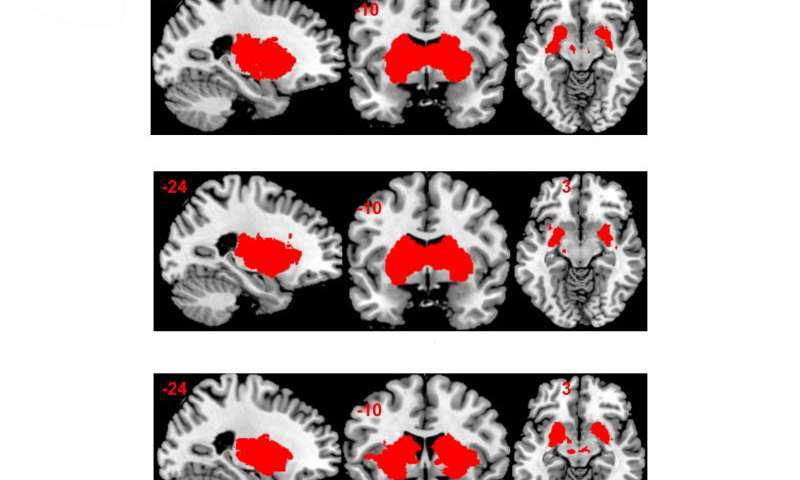

Команда исследователей университета Базеля под руководством профессоров Кристофа Beglinger и Стефана Borgwardt завершила в 2015 г исследование того, как глюкоза и фруктоза влияют на взаимодействие желудочно-кишечного тракта и [2]. Их работа финансировалась швейцарским Национальным научным Фондом.

Двенадцати здоровым молодым мужчинам давали либо фруктозу, либо глюкозу, либо плацебо через питательную трубку. У испытуемых брали образцы крови, чтобы измерить уровни гормона сытости. Испытуемые также отвечали на вопросы о том, насколько сытыми они чувствовали себя, а активность их

Результаты были следующими. В отличие от глюкозы, фруктоза была менее эффективна в создании чувства сытости и стимулирования системы вознаграждения в

«Исследование может предоставить первые обоснованные выводы об отсутствие сытости и вознаграждающего эффекта вызванного фруктозой» – подтвердили ведущие авторы исследования д-р Беттина Wölnerhanssen и д-р Анн Кристин Мейер-Gerspach.